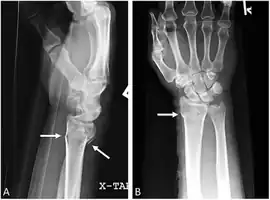

Diagnosis can be made upon interpretation of anteroposterior and lateral views alone.[6]

The classic Colles fracture has the following characteristics:[7]

- Transverse fracture of the radius

- 2.5 cm (0.98 inches) proximal to the radio-carpal joint

- dorsal displacement and dorsal angulation, together with radial tilt[8]

- Radial shortening

- Loss of ulnar inclination≤

- Radial angulation of the wrist

- Comminution at the fracture site

- Associated fracture of the ulnar styloid process in more than 60% of cases.

Bilateral Colles fractures/frontal

Bilateral Colles fractures/lateral

Colles fracture